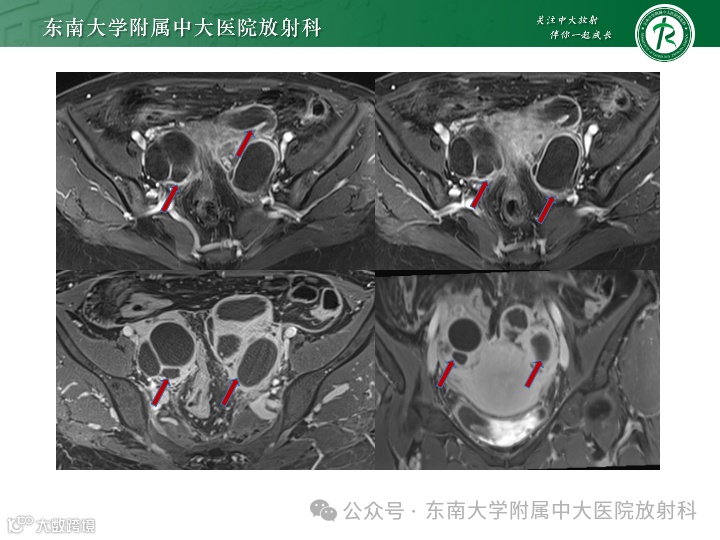

病例2

女,27岁 -

主诉:腹胀1周 -

现病史:1周前自觉腹胀,有恶心,无明显腹痛呕吐,无异常阴道出血,无腹泻便秘等,于外院就诊查CA125:791.8U/ml,左侧卵巢内见一19*18mm液性暗区,腹盆腔见深约65mm液性暗区。遂住院于腹腔穿刺,每日约1000ml左右,淡黄色,腹水脱落细胞可见淋巴细胞。今为求进一步诊治来我院就诊

影像学表现